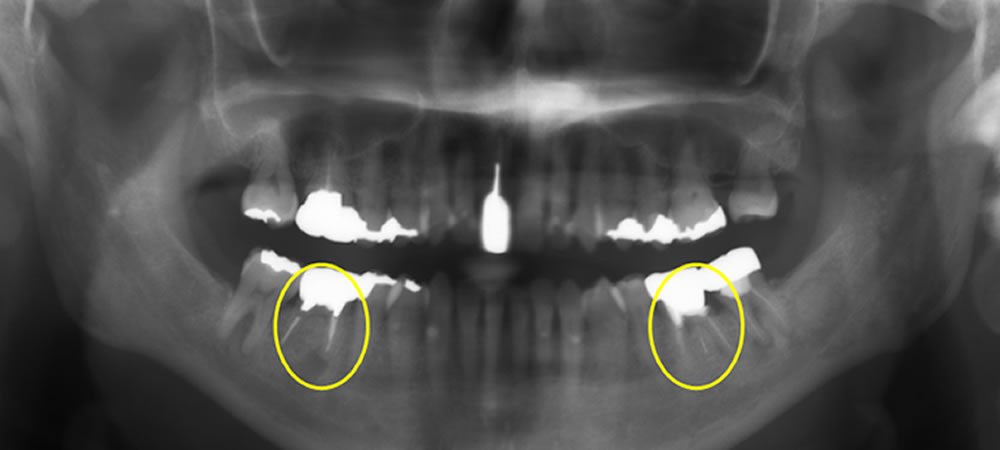

レントゲン上で右下の6番目の根の先端に大きい影が見られます。また左下も噛むと痛みがあるとのことでした。小さい根尖病巣が確認できますが、かなり大きい土台が入っていて再治療が困難な状態なため、患者さまと相談し、右下、左下の大臼歯を抜歯してインプラントで治療する計画を立てました。